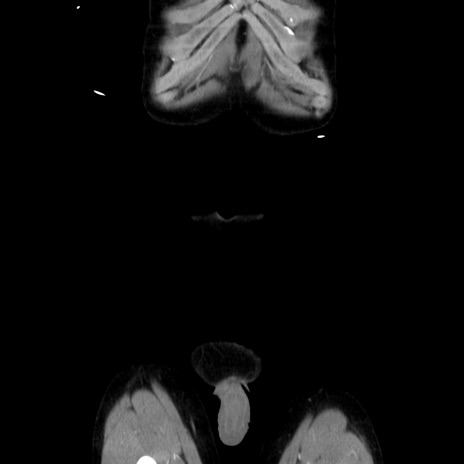

症例37(冠状断像)

【症例】40歳代 男性

【主訴】腹痛

【現病歴】4時間ほど前に電車に乗車中に臍部上より腹痛出現。徐々に増悪し起立困難となり、救急外来受診。生ものは数日食べていない。今朝お雑煮を食べた。

【身体所見】BT 36.8℃、BP 117/84mmHg、HR 91/min、SpO2 97%、苦悶様、腹部:臍上部広範囲圧痛あり、反跳痛±

【データ】WBC 8100、CRP 0.03